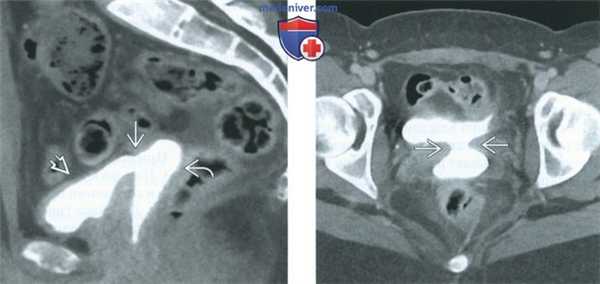

(Слева) При КТ-цистографии в сагиттальной плоскости отмечается контрастирование влагалища через свищ, открывающийся в мочевой пузырь. Пациентке незадолго до обследования была выполнена гистерэктомия.

(Справа) При КТ в аксиальной плоскости с контрастным усилением у той же пациентки выявляется широкий свищевой ход, связывающий мочевой пузырь с влагалищем. В развитых странах гинекологические операции являются частой причиной образования вагинальных свищей.